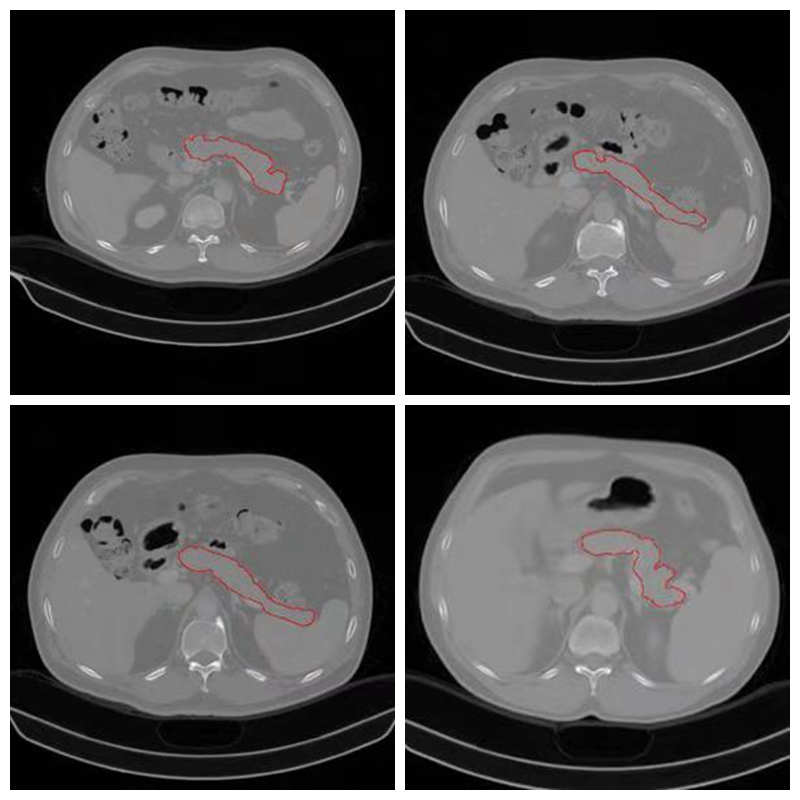

胰腺是人体最重要器官之一,具有内、外分泌功能。近年,胰腺疾病的发病率逐年上升,尤其是胰腺癌,为致死率最高的肿瘤之一,5年生存率小于1%。CT检查为诊断胰腺病变最主要的检查方式,随着数字医疗设备的进步和影像组学和深度学习等领域的发展,利用CT数据进行计算机辅助诊断,准确诊断胰腺病成为可能。而胰腺分割作为计算机辅助诊断基础而重要步骤,研究意义重大。由于胰腺的解剖结构较为复杂,其主要位于后腹膜,形态、位置变异较大,且周围有大量邻近组织,如胃、十二直肠、脾脏及大血管,这些组织在CT图像上与胰腺紧密相连且密度相似,再加上CT图像本身的噪声、局部体效应和组织运动的影响等因素,胰腺分割也是个具有很大挑战性的问题。

此次胰腺CT分割挑战赛,由ISICDM 2018会议组委会联合陆军军医大学数字医学研究所和陆军军医大学西南医院联合主办,旨在通过挑战赛的形式为数字医学产学研界提供技术交流和展示的平台。本项挑战赛收集20例经病理诊断为胰腺癌的病人,40例正常对照组(男性、女性各20例)。扫描设备为西门子64排CT(Definition AS, Siemens),扫描方案为标准胰腺扫描方案,受试者仰卧位躺于扫描床上,扫描范围上包括膈肌,下包括坐骨结节。共采集平扫、动脉期、静脉期三组数据。平扫完成后依据体重经肘静脉推注非离子造剂(欧乃派克350 GE)100-120ml,注射速度为4-5ml/s,注射完成后25-30s采集动脉期,60s采集静脉期。扫描参数为管电压120KV,有效管电流为60-110mAs,准直宽度为16x1.2mm,螺距为0.8,分别行1mm和5mm重建。因胰腺分割在临床上多采用静脉期,所以本次挑战赛仅选取了静脉期图像。

此次胰腺分割挑战赛兼具专业性和实战性。专业性不仅体现在参赛选手的教育背景和专业水准上(决赛队伍均来自浙江大学、上海交通大学、厦门大学、同济大学等中国一流高校),也体现在算法和医生评委上。决赛算法评委包括了电子科技大学的李纯明教授,美国杜兰大学的王玉平教授和平安科技美东研究院的吕乐博士。来自北京大学第一医院的王霄英教授,北京协和医院的陆菁菁教授和吉林大学第一医院的佟丹教授则组成了强大的医生评委阵容。在实战性上,参赛队伍使用的20例训练数据和16例测试数据均来自陆军军医大学西南医院的真实临床数据,每一例都包含层厚为2mm和5mm的两个增强静脉期三维CT图像,并且大赛不允许反复提交分割结果,避免了传统分割挑战赛中参赛者通过反复提交结果刷分数的弊端。据了解,王一达为了准备本次比赛,整个国庆节都在紧张的备战。初赛和决赛环节的每场比赛时间越来越短,也越来越逼近真实临床环境。在现场决赛环节,两轮初赛总成绩前十名的团队到场,自备电脑连接会场的大屏幕,评委和观众在台下实时观看参赛代表的软件操作过程,所得到的结论真实可信。